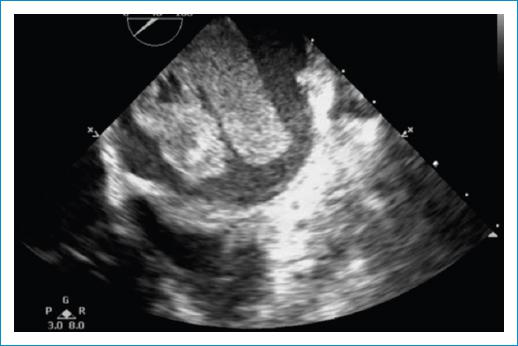

El electrocardiograma documentó único hallazgo de taquicardia sinusal. Entre los paraclínicos de ingreso se encontró INR en rangos terapéuticos (2.7) hipoalbuminemia, gases arteriales con evidencia de acidosis metabólica con anión Gap normal con hipoxemia moderada (Tabla 1) y radiografía de tórax simple con evidencia de edema pulmonar en fase intersticial (Fig. 1).Se complementó con ecocardiograma transtorácico, el cual reportó una masa en la aurícula izquierda, que parecía estar adherida a su pared posterior y obstruía el tracto de entrada del ventrículo izquierdo (Fig. 2). Fue valorada por el equipo de cirugía cardiovascular quienes indicaron la toma de ecocardiograma transesofágico, el cual permitió una mejor caracterización de la lesión; en este se halló una masa lobulada, de bordes irregulares, ecogenicidad intermedia y quistes en su interior, la cual se encontraba adherida a la parte posterior de la aurícula izquierda y a la vena pulmonar inferior derecha a través de un pedículo, comprometiendo el flujo de dicho vaso e infiltrando también su pared (Fig. 3). Esta masa protruía, también, a través del tracto de entrada del ventrículo izquierdo (Fig. 4), comprometiendo el flujo de manera significativa (velocidad pico: 2,5 m/s y gradiente medio de 14 mm Hg). Adicionalmente, el septum interauricular se encontraba tapizado por una masa de similares características (Fig. 5). A razón de dichos hallazgos, fue sometida a intervención quirúrgica, en la que se halló una masa multilobulada de características sarcomatosas de 8 cm x 4 cm con infiltración completa de la vena pulmonar derecha y oclusión del 100% de su luz; la infiltración de las paredes y la extensión hacia el hilio pulmonar hicieron imposible una resección radical, con reporte histopatológico de sarcoma indiferenciado (Fig. 3).

Figura 2 Ecocardiograma transtorácico en el que se observa masa de ecogenicidad intermedia que ocupa la aurícula izquierda y produce obstrucción del tracto de entrada del ventrículo izquierdo.